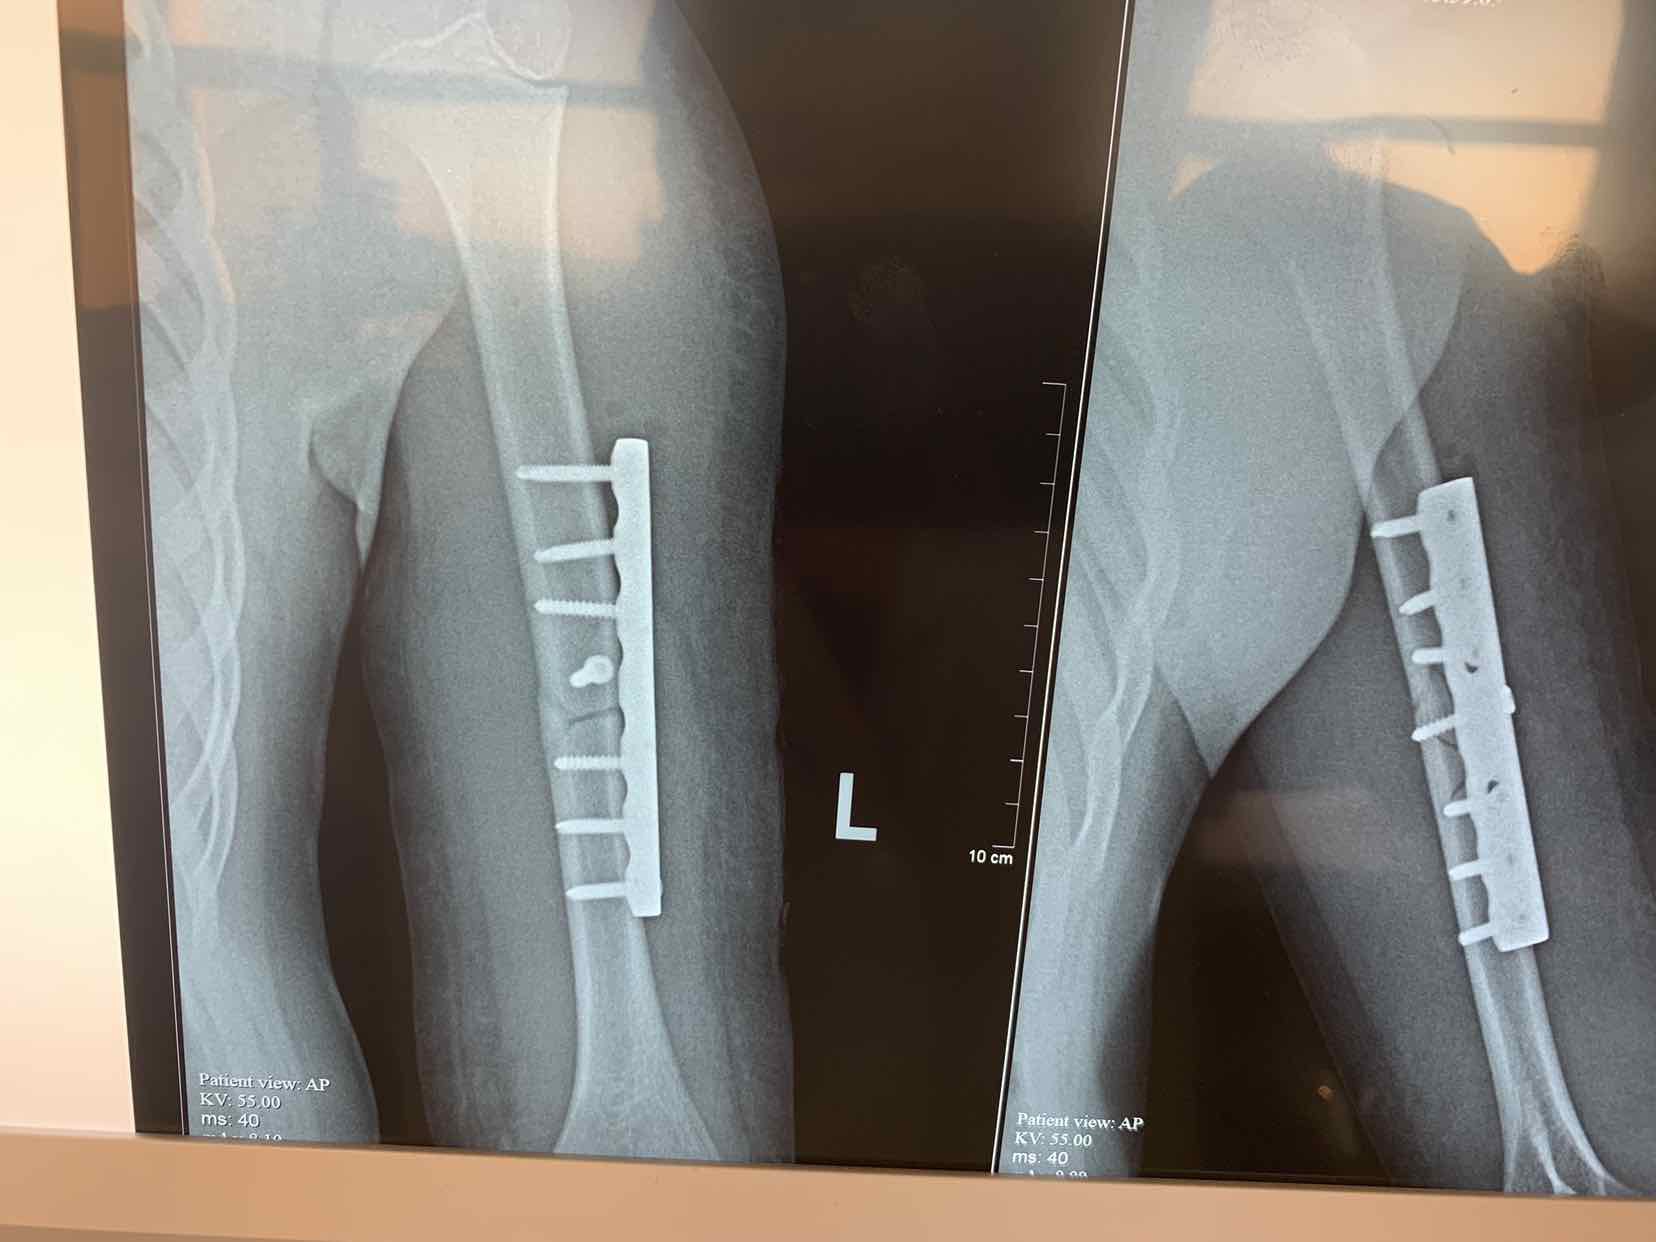

诊断为左侧肱骨中段骨折。全麻下行切开复位内固定术。术中局部应用拉力螺钉固定骨折端,安放六孔锁定钢板内固定,效果不错。术后早期就可以活动了。

对于儿童肱骨骨折只要具备手术指征,可以考虑手术,这类不稳定骨折,保守治疗容易遗留畸形愈合后遗症。早期手术早期恢复功能。